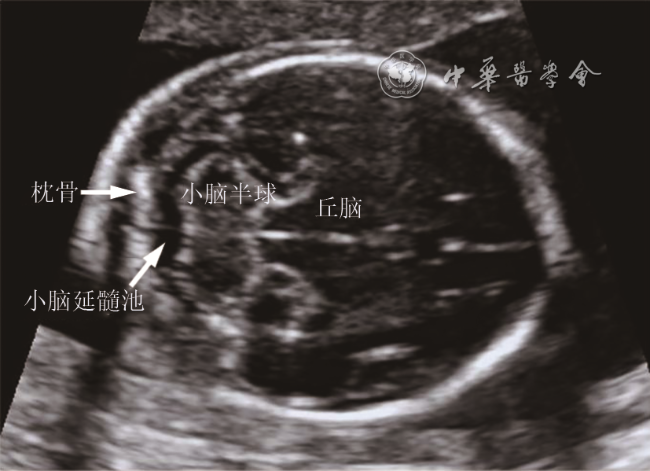

按照北京市产前超声筛查与诊断规范,对胎儿及其附属物进行系统性检查。对胎儿颅后窝进行多切面的超声扫查,对小脑半球、小脑蚓部、第四脑室、小脑延髓池、小脑幕等结构的位置、形态、大小进行观察及测量(图12)。测量方法及标准参考北京市产前超声筛查及诊断规范,所有病例均由具备产前诊断资格的超声医师完成。

图1 胎儿颅脑横切面显示小脑延髓池及周围结构

小脑延髓池(枕大池)是后颅窝蛛网膜下腔的一部分,是胎儿颅内结构的常规筛查内容。小脑延髓池宽度的超声测量方法为经小脑横切面上测量小脑蚓部后缘至枕骨内缘的距离。整个孕期小脑延髓池宽度基本恒定,正常范围为2~10 mm。虽然小脑延髓池增宽多数为单纯变异,但也有部分病例与多种预后不一的胎儿颅内结构异常相关1,因此超声筛查发现的小脑延髓池增宽是进行产前针对性检查和诊断的指征。超声检查胎儿颅内结构存在一定的局限性,容易受到胎儿体位以及颅骨声影的影响,在晚孕期胎儿尤为明显,MRI技术能够准确评估胎儿颅内结构2, 3, 4,因此,本研究以胎儿颅脑MRI为标准,评估超声对小脑延髓池增宽胎儿的诊断价值。